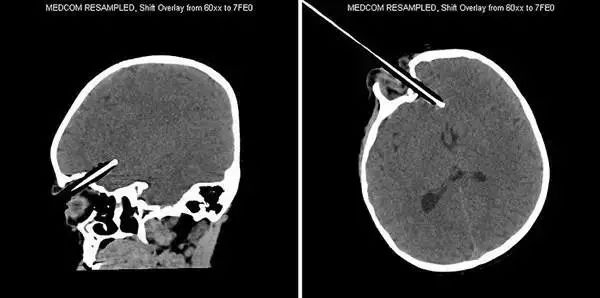

6、这把*首匕**扎入了一名仅有10岁大的阿富汗小男孩的头部,经过手术之后被取出,并在医院接受后续治疗。

7、这名不幸的患者被一根撬棍刺穿头部。

8、一名中国的69岁老人被人送往医院,X光片显示他的头顶被钉入了3根钉子。医生紧急手术将钉子取出。这位老人住院了3个月并最终康复出院。

9、这名仅有2岁大的幼童不小心跌倒,手里拿着的铅笔扎进了右眼,并刺入脑部。万幸的是它错过了眼球。医生取出了铅笔,并且奇迹般的是,这个孩子逐渐恢复,他的眼睛和大脑都没有显示后遗症的迹象。